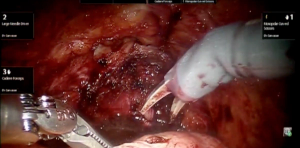

Robotic cystectomy: Y-shaped neobladder technique

This video demonstrates a technique for the intracorporeal creation of a robot-assisted Y-shaped neobladder after cystectomy.